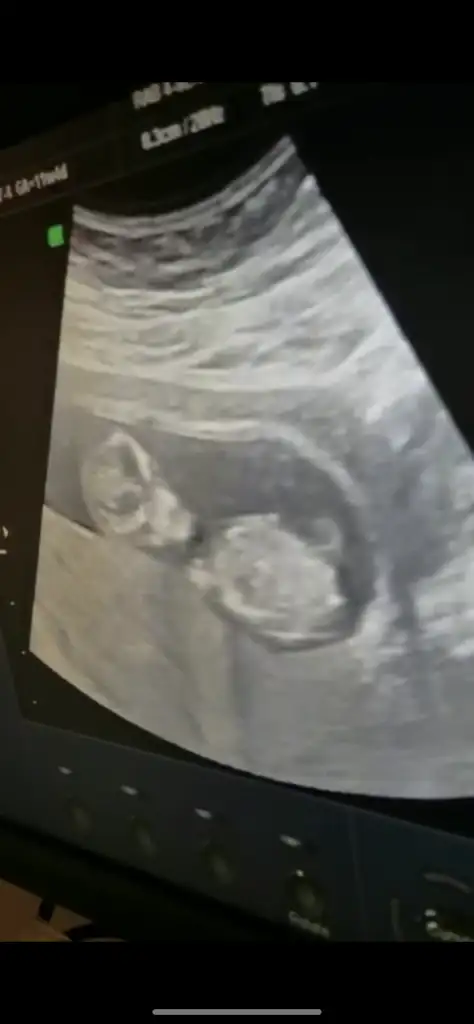

Benim bebeğim de 8 haftalık burada plasenta sağda gibi geldi. Ama yorumlayamadim.. yorumlarınızı bekliyorum ramzi teorisi ileBen neden resim paylaşamıyorum

Bu arada üstten ultrasondur. 8 haftalık ben plasentayi sağda gördüm. Yanlış görmedim isem tabi ama yorumlayamadim... Yorumlarınızı bekliyorum...Benim bebeğim de 8 haftalık burada plasenta sağda gibi geldi. Ama yorumlayamadim.. yorumlarınızı bekliyorum ramzi teorisi ile

Plasenta solda gibiBenim bebeğim de 8 haftalık burada plasenta sağda gibi geldi. Ama yorumlayamadim.. yorumlarınızı bekliyorum ramzi teorisi ile